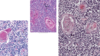

Lymph Nodes

Structure?

Comprised of what tissue?

Locations

Encapsulated structures positioned along lymphatic vessels

Reticular tissue

Axilla, Neck Vasculature, Thorax, Inguinal

Lymph Nodes

Parenchyma

Stroma

Superficial Cortex

Deep (Para) Cortex

Medulla

Lymph Flow

Hilum

Cortex + Medulla

Supportive CT

Receives lymp from afferent lymphatic vessels

Region between cortex and medulla

Sinuses converge at efferent lymphatic vessel

Exit for efferent lymphatic and exit/entry for neurovasculature

Afferent –> Cortex –> Paracortex –> Medulla –> Efferent

Exit for efferent lymphatic and exit/entry for neurovasculature

Lymph Node Cortex

Superficial Cortex: what is located here?

Deep Cortex

- Superficial

- Location of lymphatic nodules (1 & 2)

- Immune cells suspended on reticular fibers

- Deep

- Free of nodules and high in T-cell counts